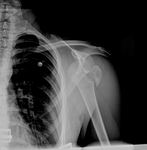

Incidência em Y escapular de radiografia mostrando uma luxação anterior de ombro

Acervo pessoal do Dr. Paul Novakovich